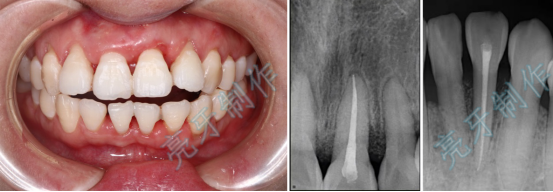

病例三:牙齿嵌入牙槽骨,松动明显,经过治疗,稳定了,也恢复了外形。

病例四:右侧前牙牙齿嵌入牙槽骨,无法咬合,治疗后,恢复功能和外形。